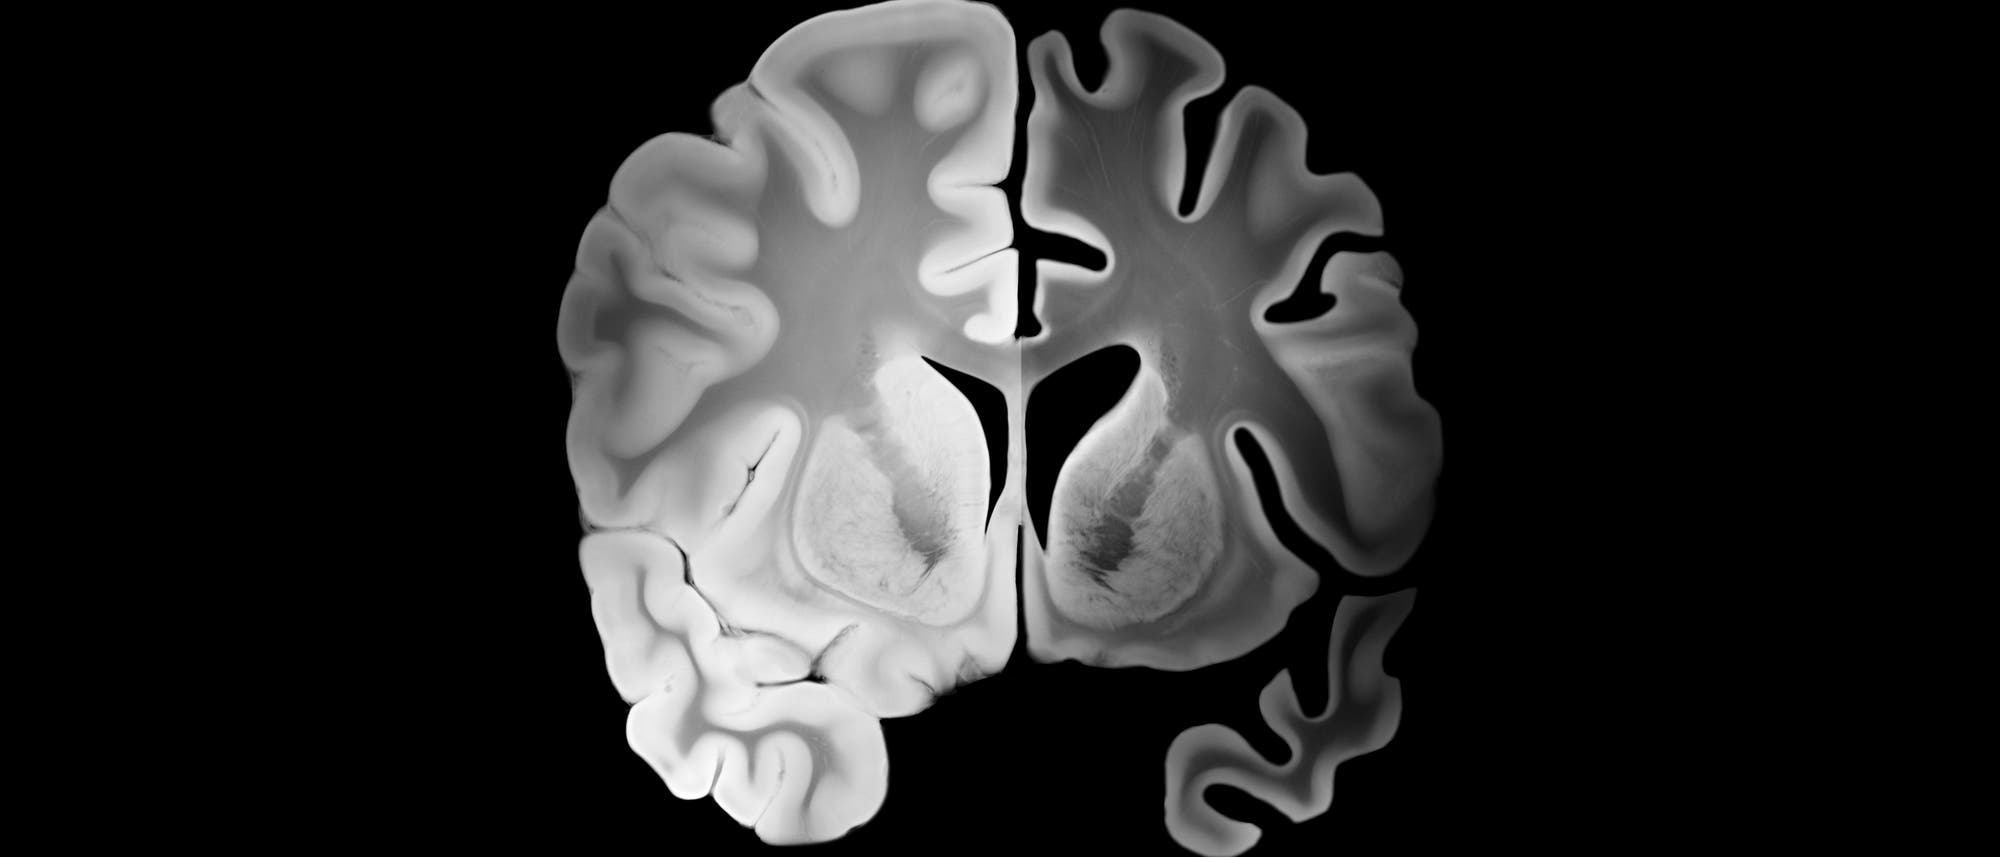

Was lässt das Gehirn altern?